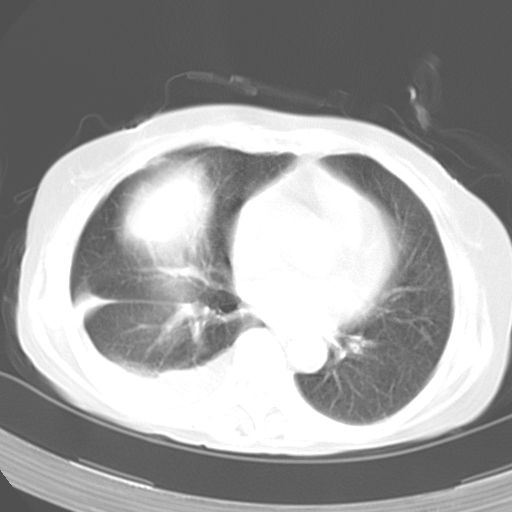

以下是引用dyqct在2006-12-7 21:08:00的发言:[br]考虑:1、肝内外胆管多发性结石伴肝左叶外侧段肝萎缩;[br] 2、右膈下多发脓肿;[br] 3、右侧少量胸腔积液、斜裂积液;[br] 4、左肾囊肿。

以下是引用jiazh在2006-12-7 20:37:00的发言:[br]肝脏周围半狐形低密度影,肝脏表面受压推移,考虑膈下脓肿可能性大;2、右侧胸腔积液

以下是引用拾荒者在2006-12-7 21:44:00的发言:[br]肝内外胆管多发结石,右膈下多发脓肿,右胸膜腔及叶间裂积液,左肾囊肿。[br] [br]